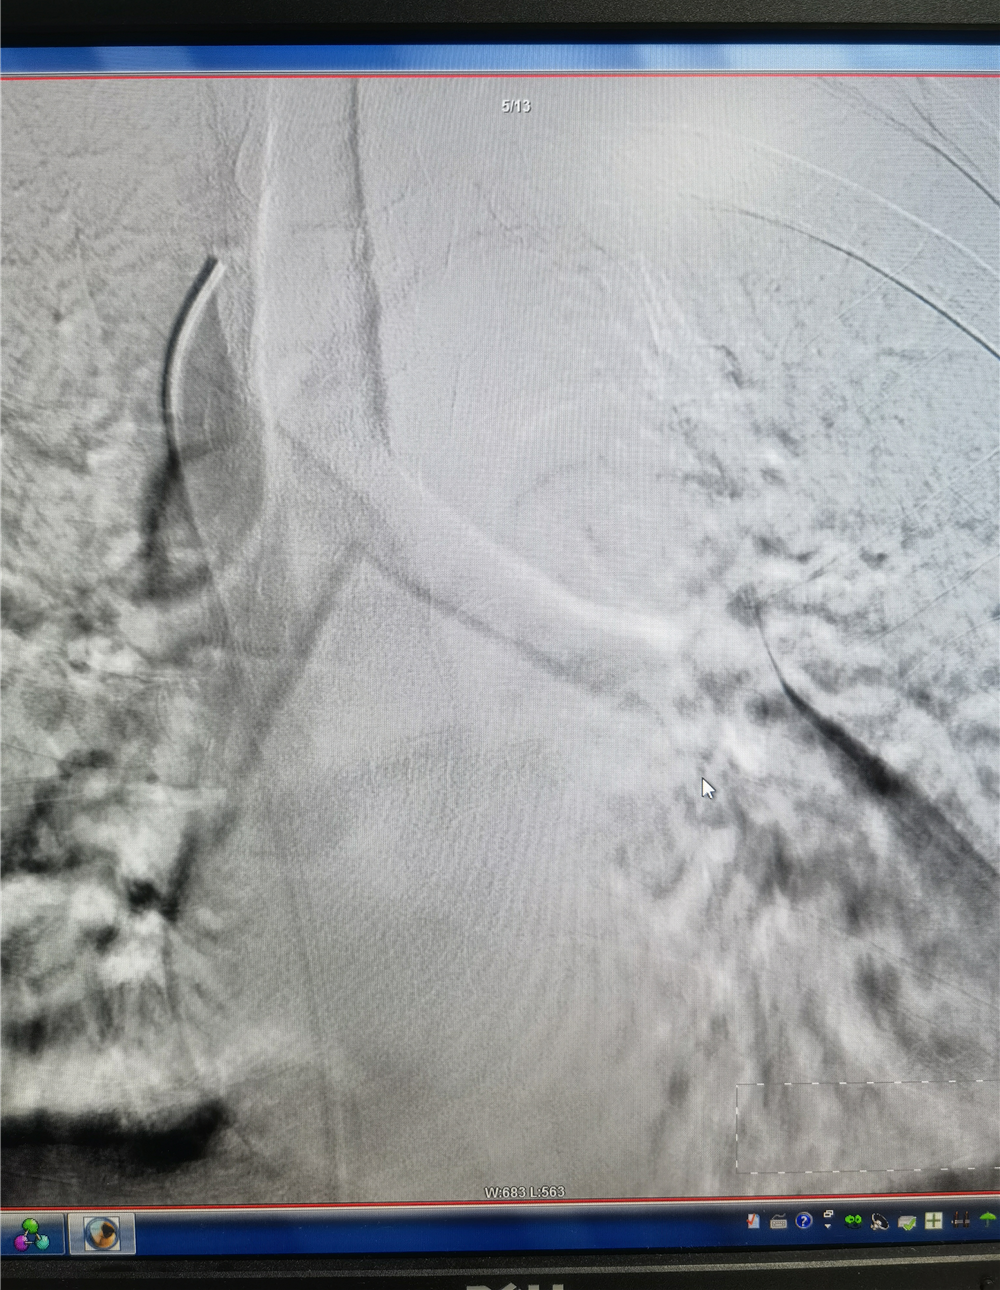

今天上午,我科刘政主任、张玉冬副主任医师、王冠主治医师会同肾病科靖永胜主任共同为田大爷进行了左头臂静脉球囊扩张成形术。术中发现患者左侧头臂静脉完全闭塞,导丝与导管正向通过阻力很大。

遂取同侧股静脉入路,将导管置于上腔静脉,造影未能显示头臂静脉汇入口,留置导管作为标记,更换加硬导丝支撑,从上肢入路顺利通过闭塞段进入上腔静脉。